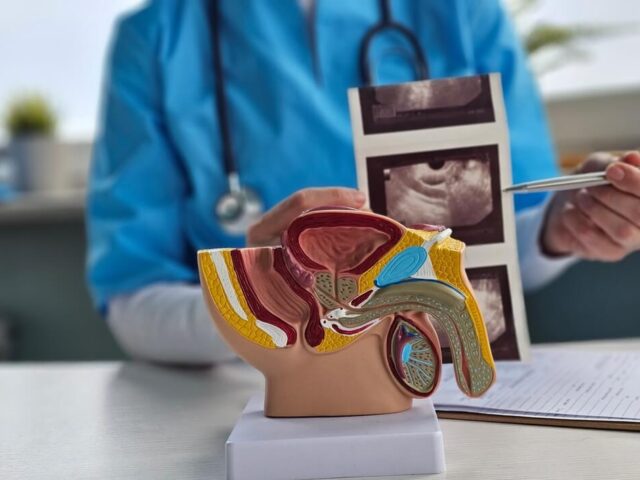

Pročitajte višeUltrazvučni pregled prostate: Kada se radi i zašto je važan za zdravlje muškaraca

Zdravlje prostate predstavlja jednu od najvažnijih tema kada je reč o muškom zdravlju, posebno nakon četrdesete godine života. Problemi sa...